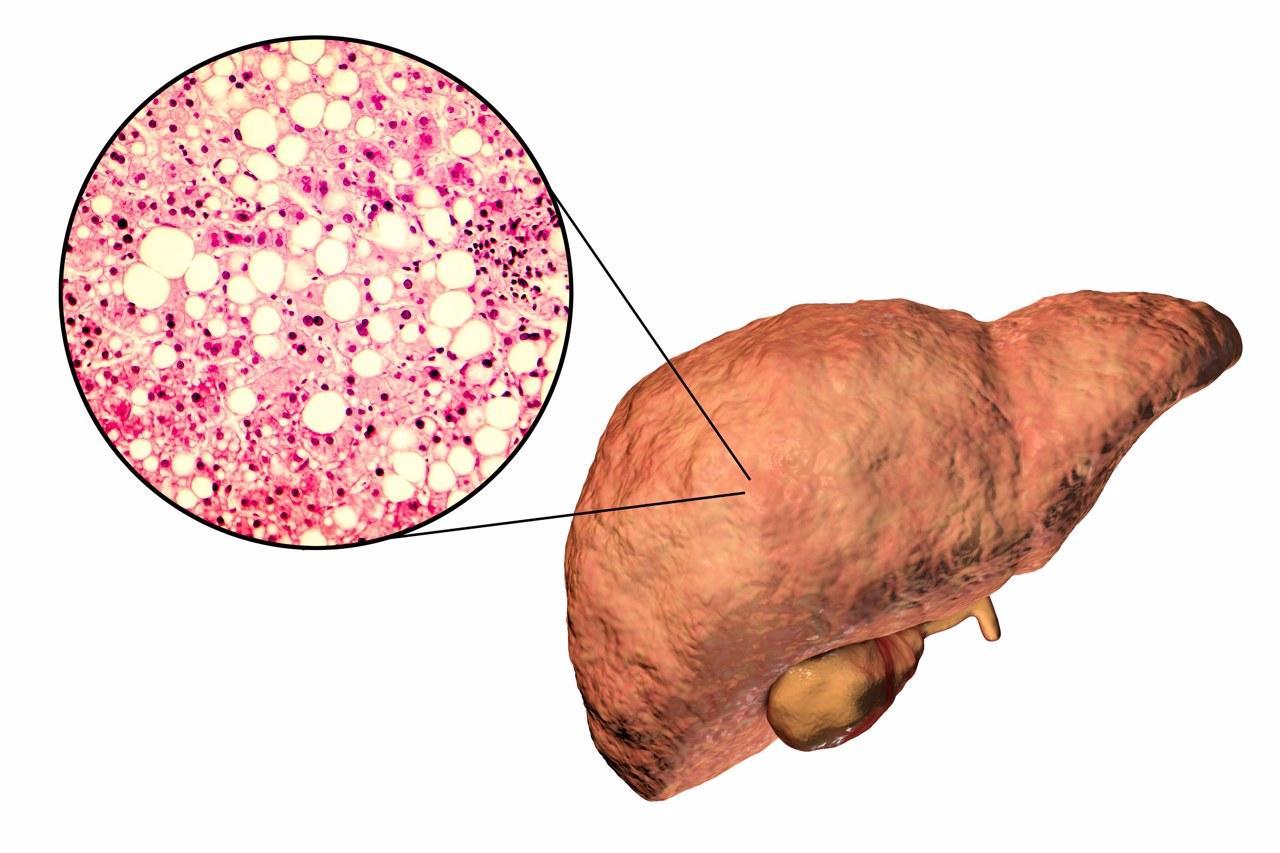

4、肝臟

肝臟是人體最大的消化器官,能夠起到解毒、代謝、分泌膽汁和參與免疫防禦的作用,是我們人體的“大型代工廠“。如果肝臟不乾淨,裏面充斥着脂肪和病毒,會有脂肪肝、乙肝等疾病,影響人體新陳代謝和身體健康。

4、肝臟乾淨——避免肥胖、避免酗酒、不亂用藥、預防乙肝

一般而言,肥胖的過程是先胖到肝,再胖到腰,最後是整體的體重超標,建議控制自己的肥胖程度,避免過胖;

肝臟處理酒精時,會產生大量的自由基,加速衰老和造成疾病;

幾乎所有藥物都要經過肝臟進行代謝,藥物及其代謝產物在肝內的濃度遠高於其他器官,因此不亂用藥可以保護肝臟;

乙肝主要通過血液傳播,無血液暴露的接觸都不會傳染乙肝,建議平時注意個人衛生,防止醫源性傳播,新生兒接種乙肝疫苗,被感染者要積極接受治療。